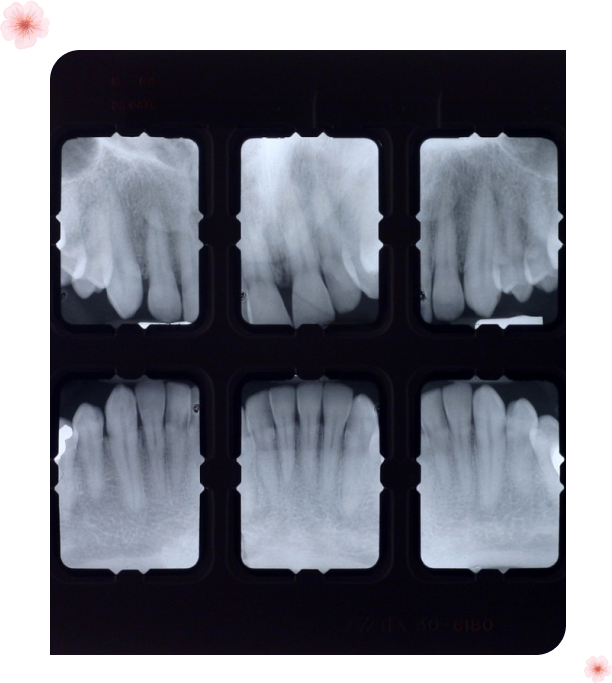

Dental X-rays

We utilize state-of-the-art dental x-rays to gain a comprehensive understanding of your oral health. These images help us detect hidden dental issues, such as cavities, impacted teeth, or bone loss, allowing for accurate diagnoses and tailored treatment plans.